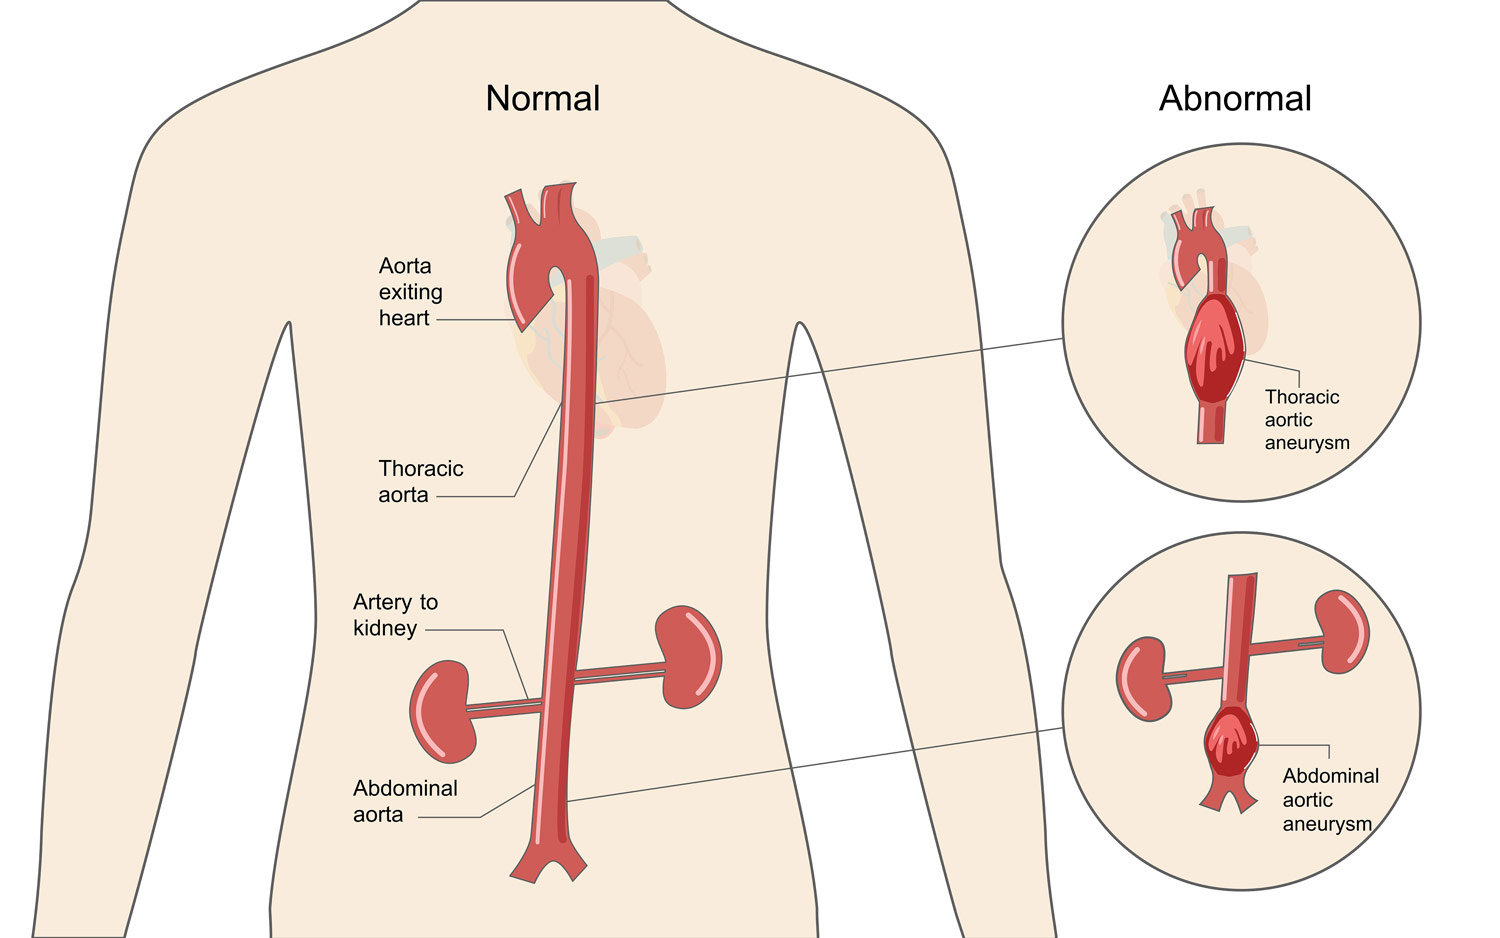

Aortic Aneurysm LaytinPride

Aortic Aneurysm LaytinPride